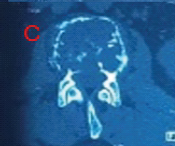

Patient post-operative follow-up at 6 months is walking comfortably without any walking aid and without any pain (Fig. 5).

Figure 5: Six-month follow-up post-operative radiograph of the left hip and full-length femur anteroposterior view shows a united fracture of both neck and shaft of the femur. There is no evidence of avascular necrosis of the head and the patient is able to walk full weight bearing without any pain.